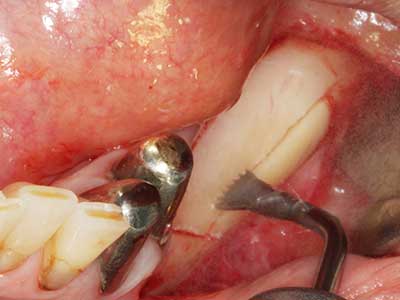

Bei der Knochenblockentnahme zeigen sich weitere Vorteile für die Piezochirurgie: Neben der bereits beschriebenen hohen Präzision bei der Osteotomie stellt sich gerade die Verwendung der dünnen Sägespitzen als besonders materialschonend heraus. Bei der Verwendung insbesondere von Lindemannfräsen sind mit deutlich höheren Entnahmeverlusten durch die dickere Instrumentenspitze zu rechnen (Lakshmiganthan, Gokulanathan et al. 2012). Die insbesondere bei retromolar entnommenen Blocktransplantaten notwendige basale Abtrennung wird durch speziell hierfür vorgesehene rechtwinklige Sägen erleichtert, so dass die Piezochirurgie als präzises, übersichtliches und sicheres Verfahren zur retromolaren Knochenblockgewinnung angesehen wird (Happe 2007) (Abb. 1-12).

Sollen chirurgische Eingriffe mit unmittelbarer Knochenbeziehung an empfindlichen Strukturen wie Blutgefäßen oder Nerven erfolgen, so bergen rotierende Instrumente ein erhebliches Potential an iatrogener Schädigung. Gerade bei Nervdarstellungen nach iatrogener Schädigung, oder aber im Zuge einer Nervlateralisation für resektive und rekonstruktive Eingriffe oder Implantatinsertionen können piezoelektronische Geräte hilfreich sein Knochendeckel zu präparieren und nervnahe Hartgewebsanteile zu entfernen (Abb. 17-20). Ein leichter Kontakt des Nervstrangs zur Piezospitze bleibt dabei in der Regel folgenlos – allerdings kann eine unvorsichtige Vorgehensweise mit sägeartigen Bewegungen bzw. Ansätzen bei noch vorhandener knöcherner Unterlage durchaus temporäre oder aber auch permanente Nervschädigungen verursachen. Das Risiko einer solchen Schädigung wird jedoch als wesentliche geringer eingeschätzt als unter Anwendung von Säge- oder Fräsinstrumenten (Pereira, Gealh et al. 2014).